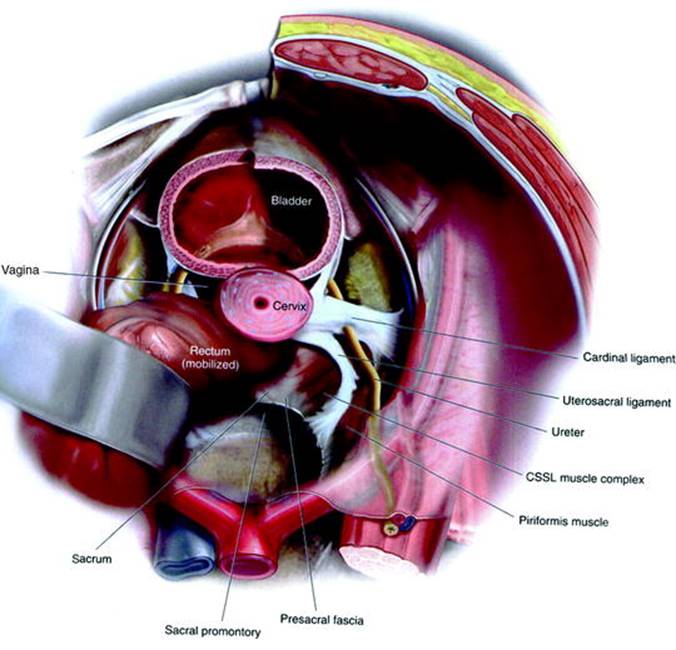

Ureteral obstruction is a known complication of uterosacral vaginal vault suspension (USVVS), usually related to kinking of the ureter during plication of the uterosacral ligament to the vaginal cuff. The distal uterosacral ligament is intimately involved with the cardinal ligament—which contains the uterine vessels—and lies in close proximity to the ureter. Anatomic studies of the ligament demonstrate that the middle and proximal segments may be ideal for use in apical suspension, with the mean ± SD distance from the ureter 0.9 ± 0.4 cm distally, 2.3 ± 0.9 cm in the middle segment, and 4.1 ± 0.6 cm proximally (Fig. 5.1) [1]. Obstruction can occur in up to 11% of procedures [2], but the incidence is markedly reduced by performing cystoscopy at the conclusion of the procedure. Indigo carmine is injected intravenously, and cystoscopy is performed to visualize efflux of blue dye from each ureter. If a strong ureteral jet is seen from both sides after the vault suspension has been completed, then ureteral obstruction is unlikely. A study of hysterectomies showed that cystoscopy is cost-effective when the rate of injury is at least 2% [3], and intraoperative as opposed to postoperative diagnosis of ureteral obstruction substantially reduces morbidity [4].

Fig. 5.1

Abdominal view illustrating the relationship between the ureter and the uterosacral ligament. Proceeding cephalad, the uterosacral ligament proceeds medially while the ureter proceeds laterally. Vault suspension to the proximal third therefore has the lowest rate of ureteral obstruction. Illustration from [38]